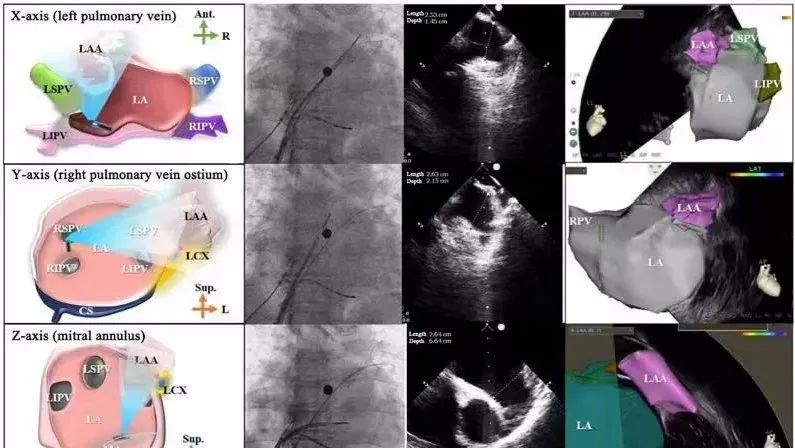

一種與心導(dǎo)管檢查相結(jié)合的超聲心動(dòng)圖診斷新興技術(shù),通過(guò)將超聲探頭置于心腔內(nèi)部,發(fā)射并接收超聲信號(hào),來(lái)精確獲取心臟解剖結(jié)構(gòu)、心臟血流動(dòng)力學(xué)等信息的實(shí)時(shí)成像。與其他影像技術(shù)相比,ICE技術(shù)具有操作簡(jiǎn)單、無(wú)輻射、安全性高、手術(shù)效率高、實(shí)用等優(yōu)勢(shì),ICE在很大程度上有望取代經(jīng)食道超聲心動(dòng)圖(TEE),成為電生理和結(jié)構(gòu)性心臟病領(lǐng)域的理想成像方式。

目前ICE技術(shù)已被應(yīng)用于左心耳封堵、房顫射頻消融、二尖瓣成形、房間隔缺損封堵等多種心臟介入手術(shù),應(yīng)用場(chǎng)景主要圍繞臟電生理、結(jié)構(gòu)性心臟病等領(lǐng)域,目前以電生理應(yīng)用為主。數(shù)據(jù)顯示,我國(guó)結(jié)構(gòu)性心臟病介入器械市場(chǎng)規(guī)模已從2017年的4億元增長(zhǎng)至2021年的20億元,年復(fù)合增長(zhǎng)率達(dá)48.3%;預(yù)計(jì)到2025年,該市場(chǎng)規(guī)模將達(dá)到104億元,可以預(yù)見(jiàn)ICE市場(chǎng)規(guī)模也將同步高速增長(zhǎng),未來(lái)市場(chǎng)發(fā)展空間廣闊。

心腔內(nèi)超聲(ICE)技術(shù)壁壘極高,國(guó)內(nèi)主要廠商核心部件仍舊為進(jìn)口,集成了超聲和圖像處理最前端技術(shù),包括超聲探頭、線纜、軟件成像算法等,是當(dāng)前內(nèi)窺超聲方向最具挑戰(zhàn)的領(lǐng)域。ICE的應(yīng)用經(jīng)歷了2D平面成像、3D三維立體成像、以及4D的實(shí)時(shí)三維立體成像階段。